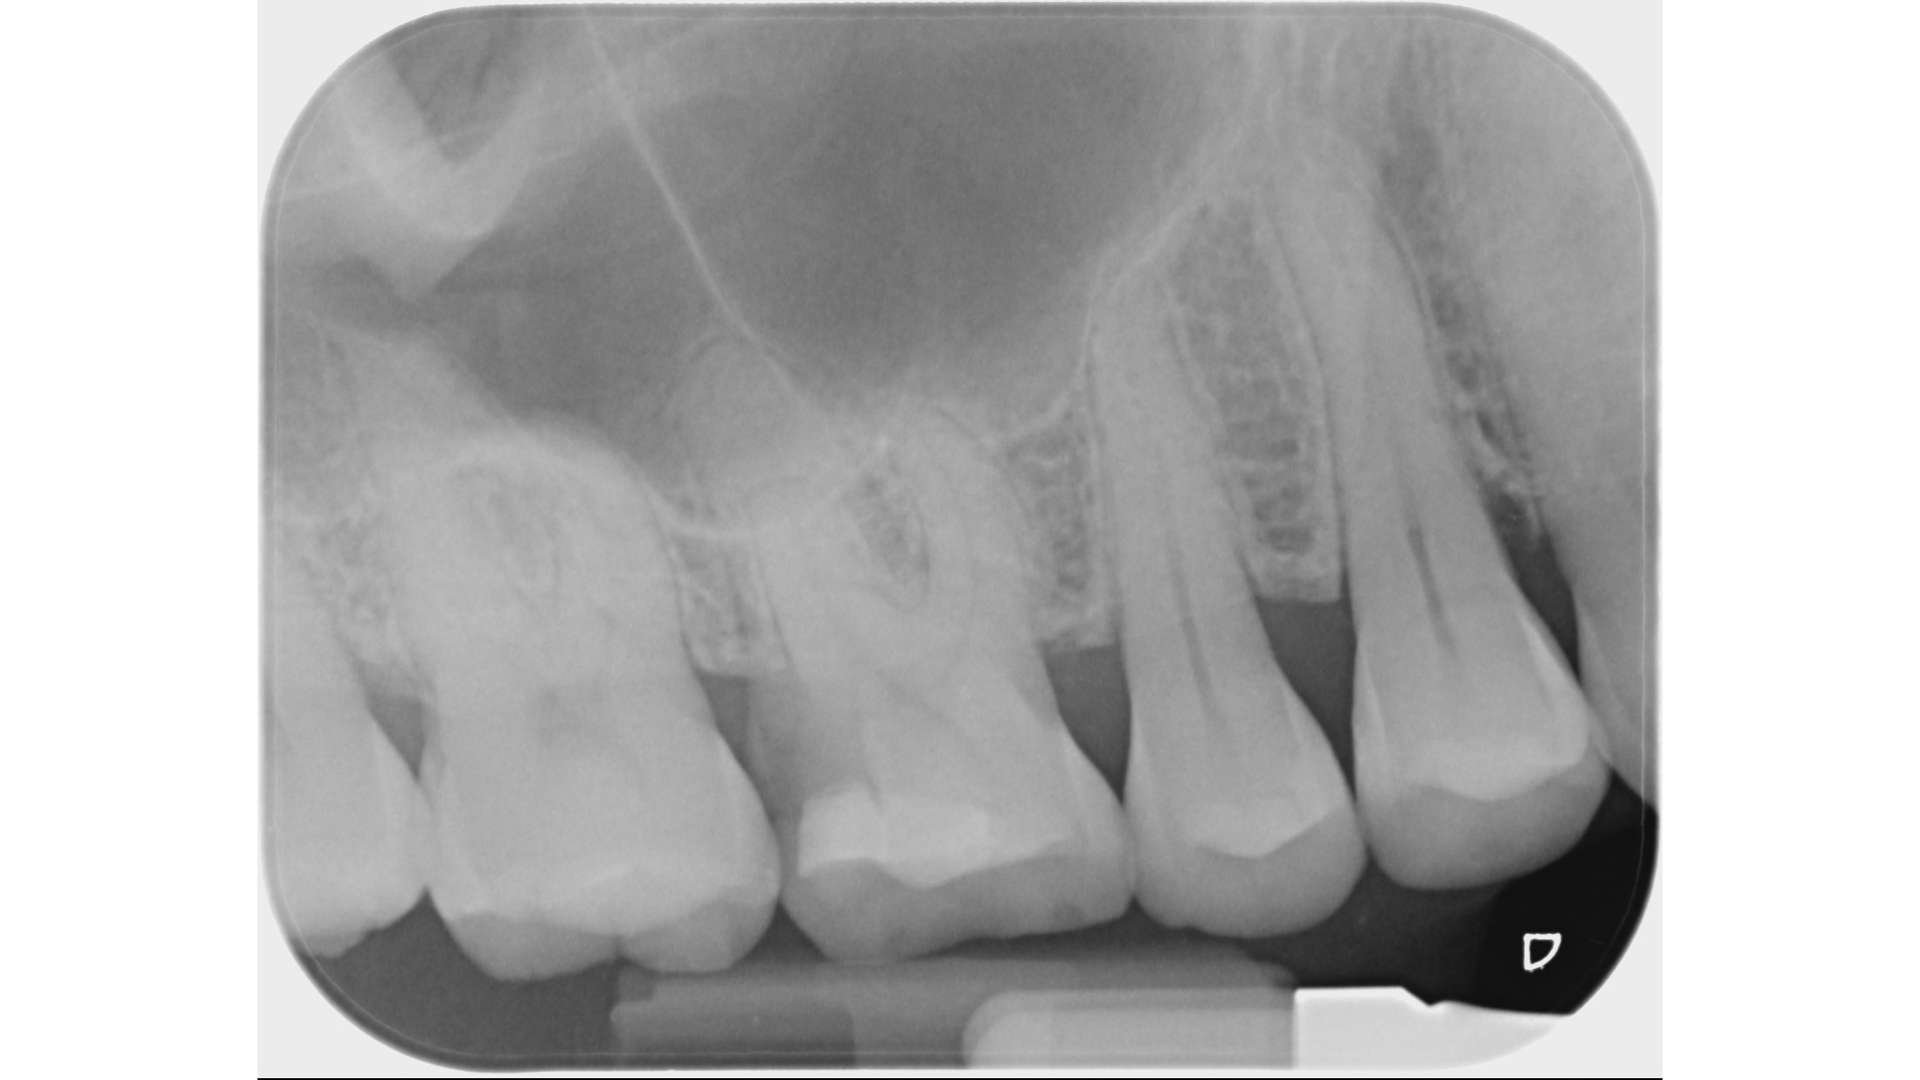

X光發現裂痕延伸到接近骨頭